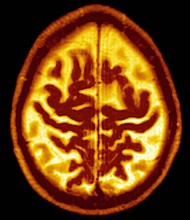

Late Onset Alzheimer's Disease Senile Dementia. Symmetric Enlargement Of Cerebral Sulci Suggests That Cortical Gray Matter Is Affected. Published on January 29, 2019 |